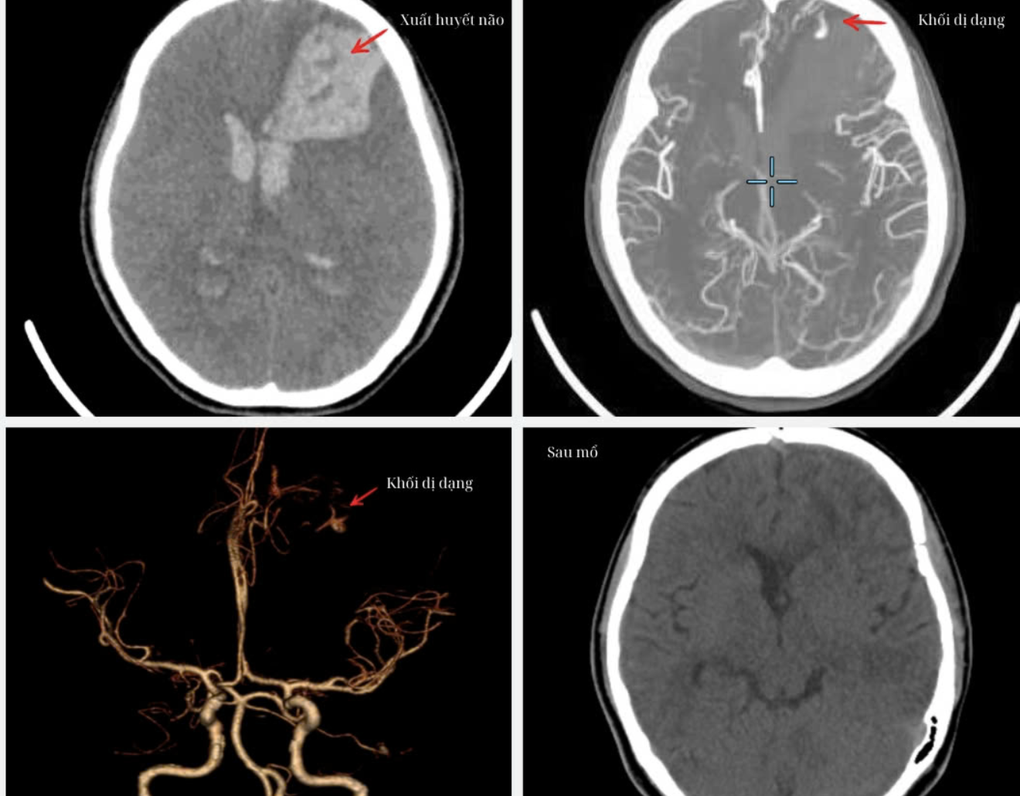

Kết quả chụp chiếu mạch máu não cho thấy V. bị xuất huyết não vùng trán trái do vỡ dị dạng mạch máu não. Máu đã tràn vào não thất, đường giữa bị đẩy lệch 10mm, não thất giãn cấp tính.

Hình ảnh chụp chiếu cho thấy tình trạng xuất huyết não và dị dạng mạch máu của bệnh nhân (Ảnh: BV).

Vào 3h sáng, ê-kíp phẫu thuật gồm hàng chục thành viên đã tranh thủ từng phút, thận trọng trong từng thao tác để lấy toàn bộ khối máu tụ, xử trí dị dạng và đặt dẫn lưu não thất.